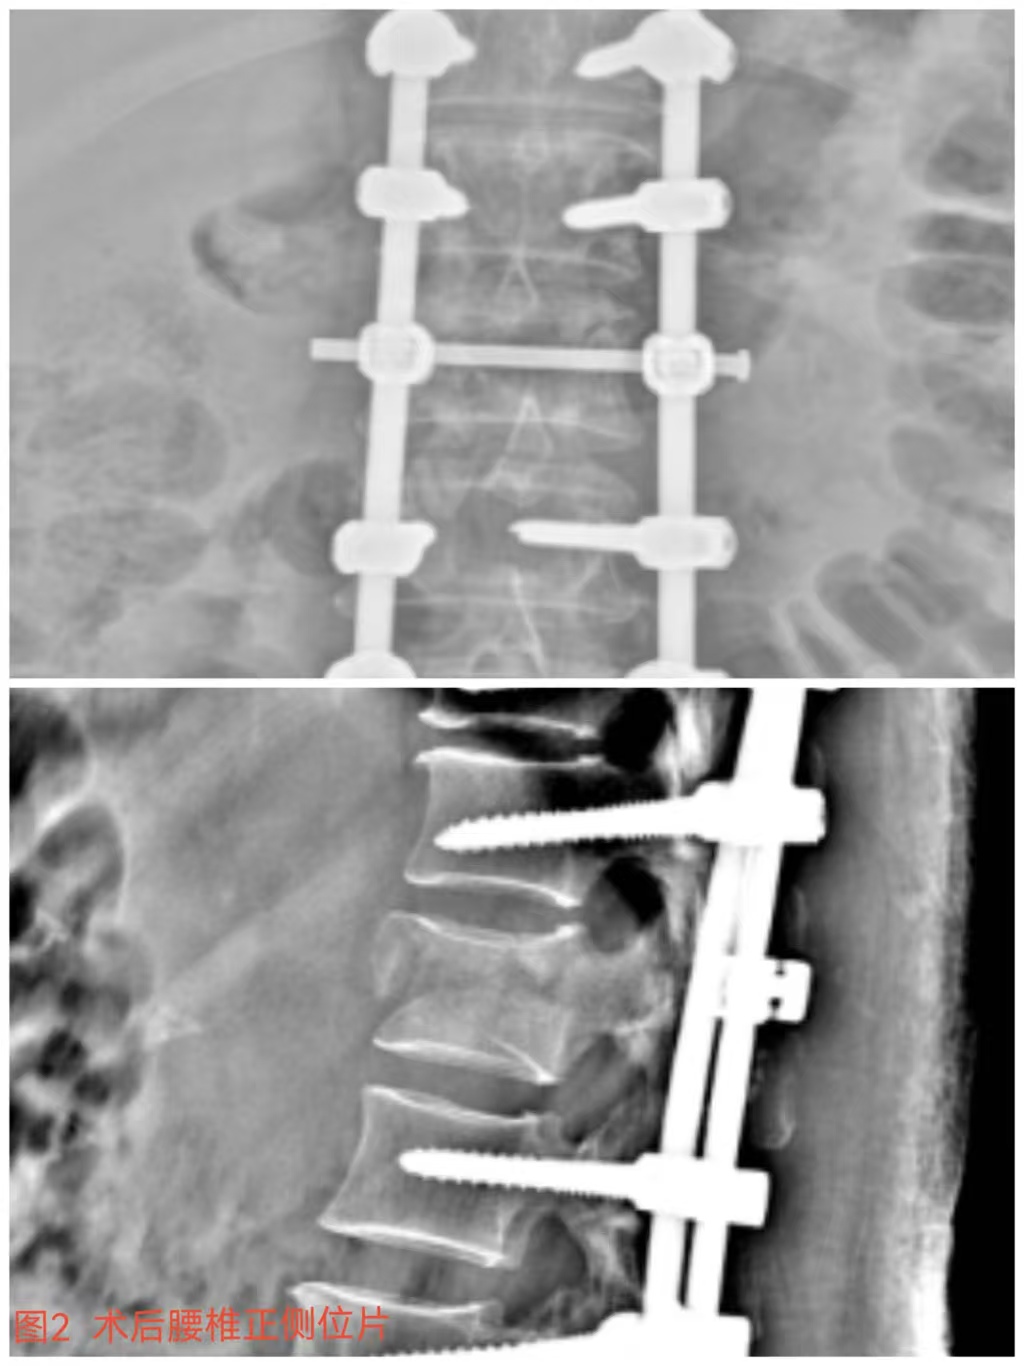

俞德亮副主任醫師深知病情的嚴重性,拖得時(shí)間越久,脊髓神經(jīng)損傷癥狀越難以恢復,必須把握住早期減壓手術(shù)的關(guān)鍵時(shí)間窗,緊急帶領(lǐng)創(chuàng )傷骨科醫師團隊對該病情進(jìn)行討論、制定手術(shù)方案,并成功為患者急診行“L1椎體爆裂性骨折伴截癱切開(kāi)椎板切除+椎管探查減壓+骨折復位釘棒系統內固定術(shù)(圖2)”,該手術(shù)精確解除對脊髓神經(jīng)的壓迫,并通過(guò)椎弓根螺釘內固定系統對受損的腰椎提供穩固的支撐,為后期的康復創(chuàng )造了良好的條件。